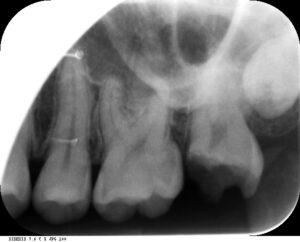

40歳男性の二次虫歯を顕微鏡根管治療